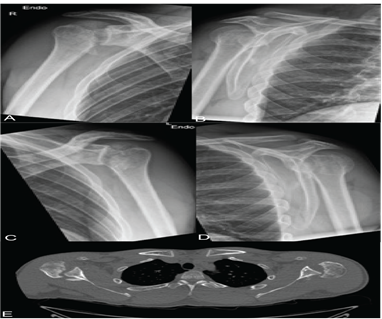

The present study describes the novel technique performed in 4 patients (mean age 29 years) with a chronic posterior locked shoulder dislocation, including 1 patient with a bilateral posterior locked shoulder dislocation. Two patients presented with a concurrent fracture of the proximal humerus, in which the posterior shoulder dislocation was initially missed. In all patients, physical examination of the upper extremities elicited shoulder pain with limited passive range of motion. Neurovascular examination was otherwise normal. Radiographs and computed tomography (CT) scan were obtained in our standard preoperative work-up, and indicated a posterior locked shoulder dislocation with a medium size reverse Hill-Sachs lesion (impaction of 25%-40% of the humeral head articular surface) (Figure 1).

Figure 1: Radiographs of the right (A-B) and left (C-D) shoulder of a 28-year-old patient with a bilateral posterior locked glenohumeral dislocation, showing the humeral head articular surface projected beyond the glenoid edge. Computed tomography (CT) confirming posterior dislocation of the humeral head with impaction on the glenoid resulting in a reverse Hill Sachs lesion (E).